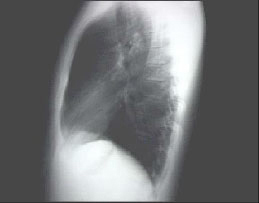

PA and Lateral

Click on the Xrays to enlarge them.

Choose the best interpretation of the chest X rays:

Straight back

Entirely normal

Rib notching

Right-sided aortic arch

Dextrocardia